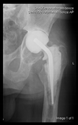

The radiological examination allowed us to verify the close bone-to-implant contact and the unchanged position of the implant during follow-up.

In all the cases operated with the above-described targeting procedure, the stems of the cups remained between the cortical bone surfaces without perforation of the linea terminalis, as shown by postoperative radiographs. There were no complicated surgical situations. In 16 cases, the wound healings were uneventful, and the hips were able to bear weight again after postoperative rehabilitation.